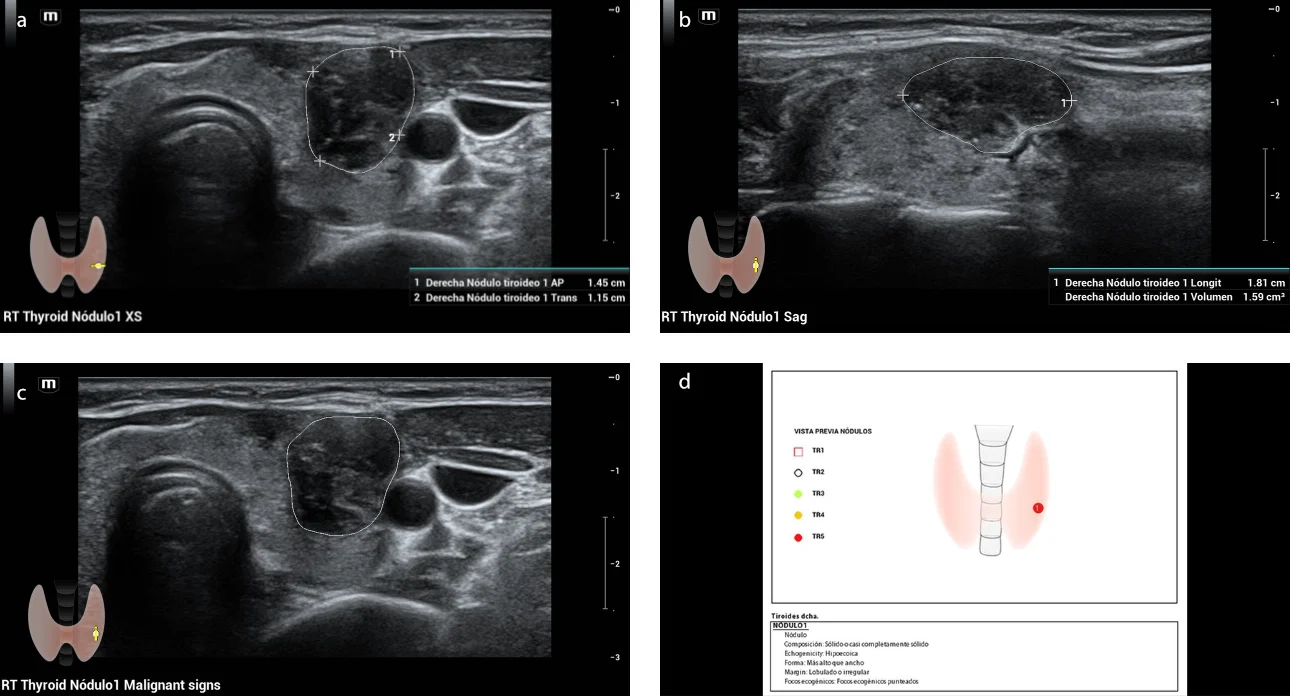

Fig. 1. US in grayscale axial section (a) and sagittal (b) shows a nodule in the middle third of the left thyroid lobe, solid, hypoechoic, wider than high, with apparent extrathyroid extension and pointed echogenic foci, measures approximately 1.3 x 1.3 x 2.1 cm, evaluated as ACR TI-RADS 5. At the application of color Doppler (c) shows internal vascularity.

Fig. 2. Evaluation of thyroid nodule by artificial intelligence program Smart Thyroid, shows nodule in the middle third of the left thyroid lobe, solid, hypoechoic, wider than high, lobed or irregular edges and pointed echogenic foci, measures approximately 1.1 x 1.4 x 1.8 cm (a,b), evaluated as ACR TI-RADS 5.8(c ,d)

During the diagnostic process, thyroid ultrasound was performed using the Mindray Resona I9 system. A solid, hypoechoic nodule was observed on the left side which was wider than high and had apparent extrathyroid extension and punctate echogenic foci. Additionally, internal vascularity was observed upon application of color Doppler. This nodule was evaluated as ACR TI-RADS 5 based on the findings (Fig. 1). Similarly, the Smart Thyroid AI of Resona i9 ultrasound system program was used to measure and analysy malignant signs and yielded comparable findings, except for the extrathyroidal extension which was assessed as having lobed/irregular borders. However, it also garnered an ACR TI-RADS 5 score (Fig. 2). The elastography examination indicated a heterogeneous appearance with an Emax stiffness of 40.53 kPa . Finally, the CEUS revealed that the lesion was heterogeneously iso-enhanced in comparison with thyroid parenchyma that showed early washout at 45 seconds (Fig. 3). The central portion of the nodule achieved peak intensity of 26.7 dB at 26.8 seconds, correspondingly; while the peripheral portion achieved peak intensity of 29.1 dB at 22.3 seconds (Fig. 4 ). The patient underwent Fine Needle Aspiration (FNA), which yielded a histopathological report of category VI of the Bethesda system, indicating papillary thyroid carcinoma. Additionally, confirmation of invasion in the prethyroid muscles was obtained during the surgical procedure.